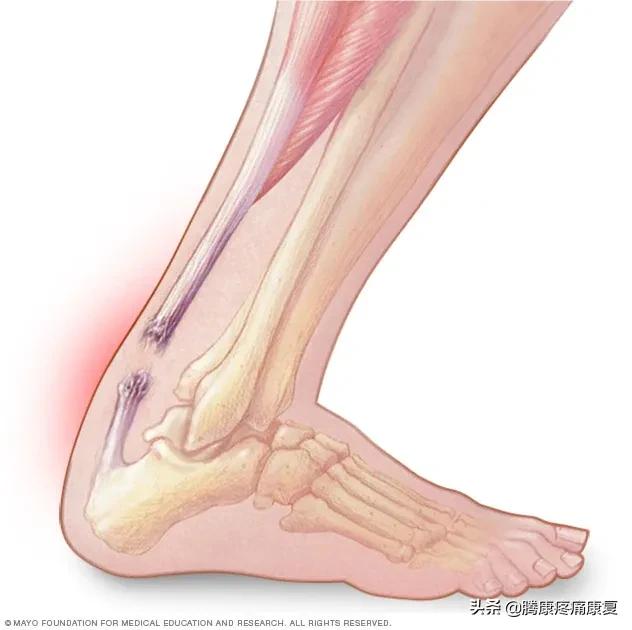

跟腱炎或断裂

跟腱是人体最大的肌腱,它位于腿部后侧,连接小腿肌肉和脚跟骨。

当肌腱受到刺激时,通常是由于过度使用,可能会感觉到腿后部的灼痛,通常就在脚跟上方。也可能有小腿疼痛和僵硬感,这就是众所周知的跟腱炎。

老人小腿疼痛是什么原因,小腿疼痛是什么原因引起的

当跟腱肌腱撕裂时,腿后部可能会突然出现剧烈疼痛。腿可能很难承受任何重量。有些人在受伤时还会听到“砰”的一声。